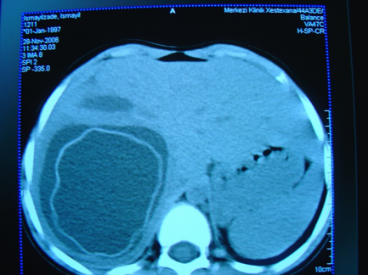

- Görüntüləmədə I seqment hipertrofiyası (yüksək şübhə əlaməti)

- Diaqnozu dəqiqləşdirmək üçün Qc venaları yoxlanılmalıdır. Bunun üçün dopler USM, KT-angioqrafiya, MRT-angioqrafiyalar və ya kontrastlı venoqrafiya edilir.

- Görüntüləmədə Qc venalarının trombotik tutulması diaqnozu dəqiqləşdirən əlamətdir.

- Görüntüləmədə qaraciyər venalarının tıxanması

Baddi-Kiari sindromu böyük qaraciyər venalarının tıxanması nəticəsində meydana gələn venoz durğunluqdur, qaraciyər venaları ilə yanaşı aşağı boş venada da tıxanma ola bilir. Tromboz, fibroz, membran və infiltrasiya (şişlər, iltihab) ən çox rast gələn səbəbləridr. Erkən mərhələlərdə kəskin hepatit və kəskin qaraciyər yetməzliyi, xroniki mərhələdə sirroz və PH meydana gələ bilir. Diaqnozu üçün tomoqrafiya və kontrastlı angioqrafiya lazım gəlir, Qc venalarının trombotik tutulması diaqnozu təsdiqləyir. digər xarakterik əlaməti birinci seqmentin hipertrofiyasıdır. Erkən mərhələdə dekompressiya (cərrahi və stend) sirroz əmələ gəldikdə isə transplantasiya ön planda tutulur.

Qaraciyər venalarının görünməməsi, kontrastlaşmaması və ya trombla tıxanması.

- Görüntüləmədə qaraciyər venalarının tıxanması, I seqment hipertrofiyası ola bilər (xroniki forma);